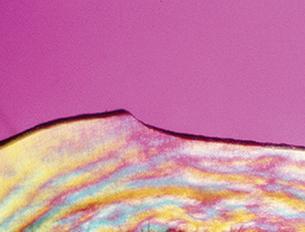

MARGINAL RETENTION AND MICROLEAKAGE

UltraSeal XT hydro Sealant

No microleakage. Sealed margins.

Competitor Hydrophilic Sealant

Microleakage. Peeling from margins.